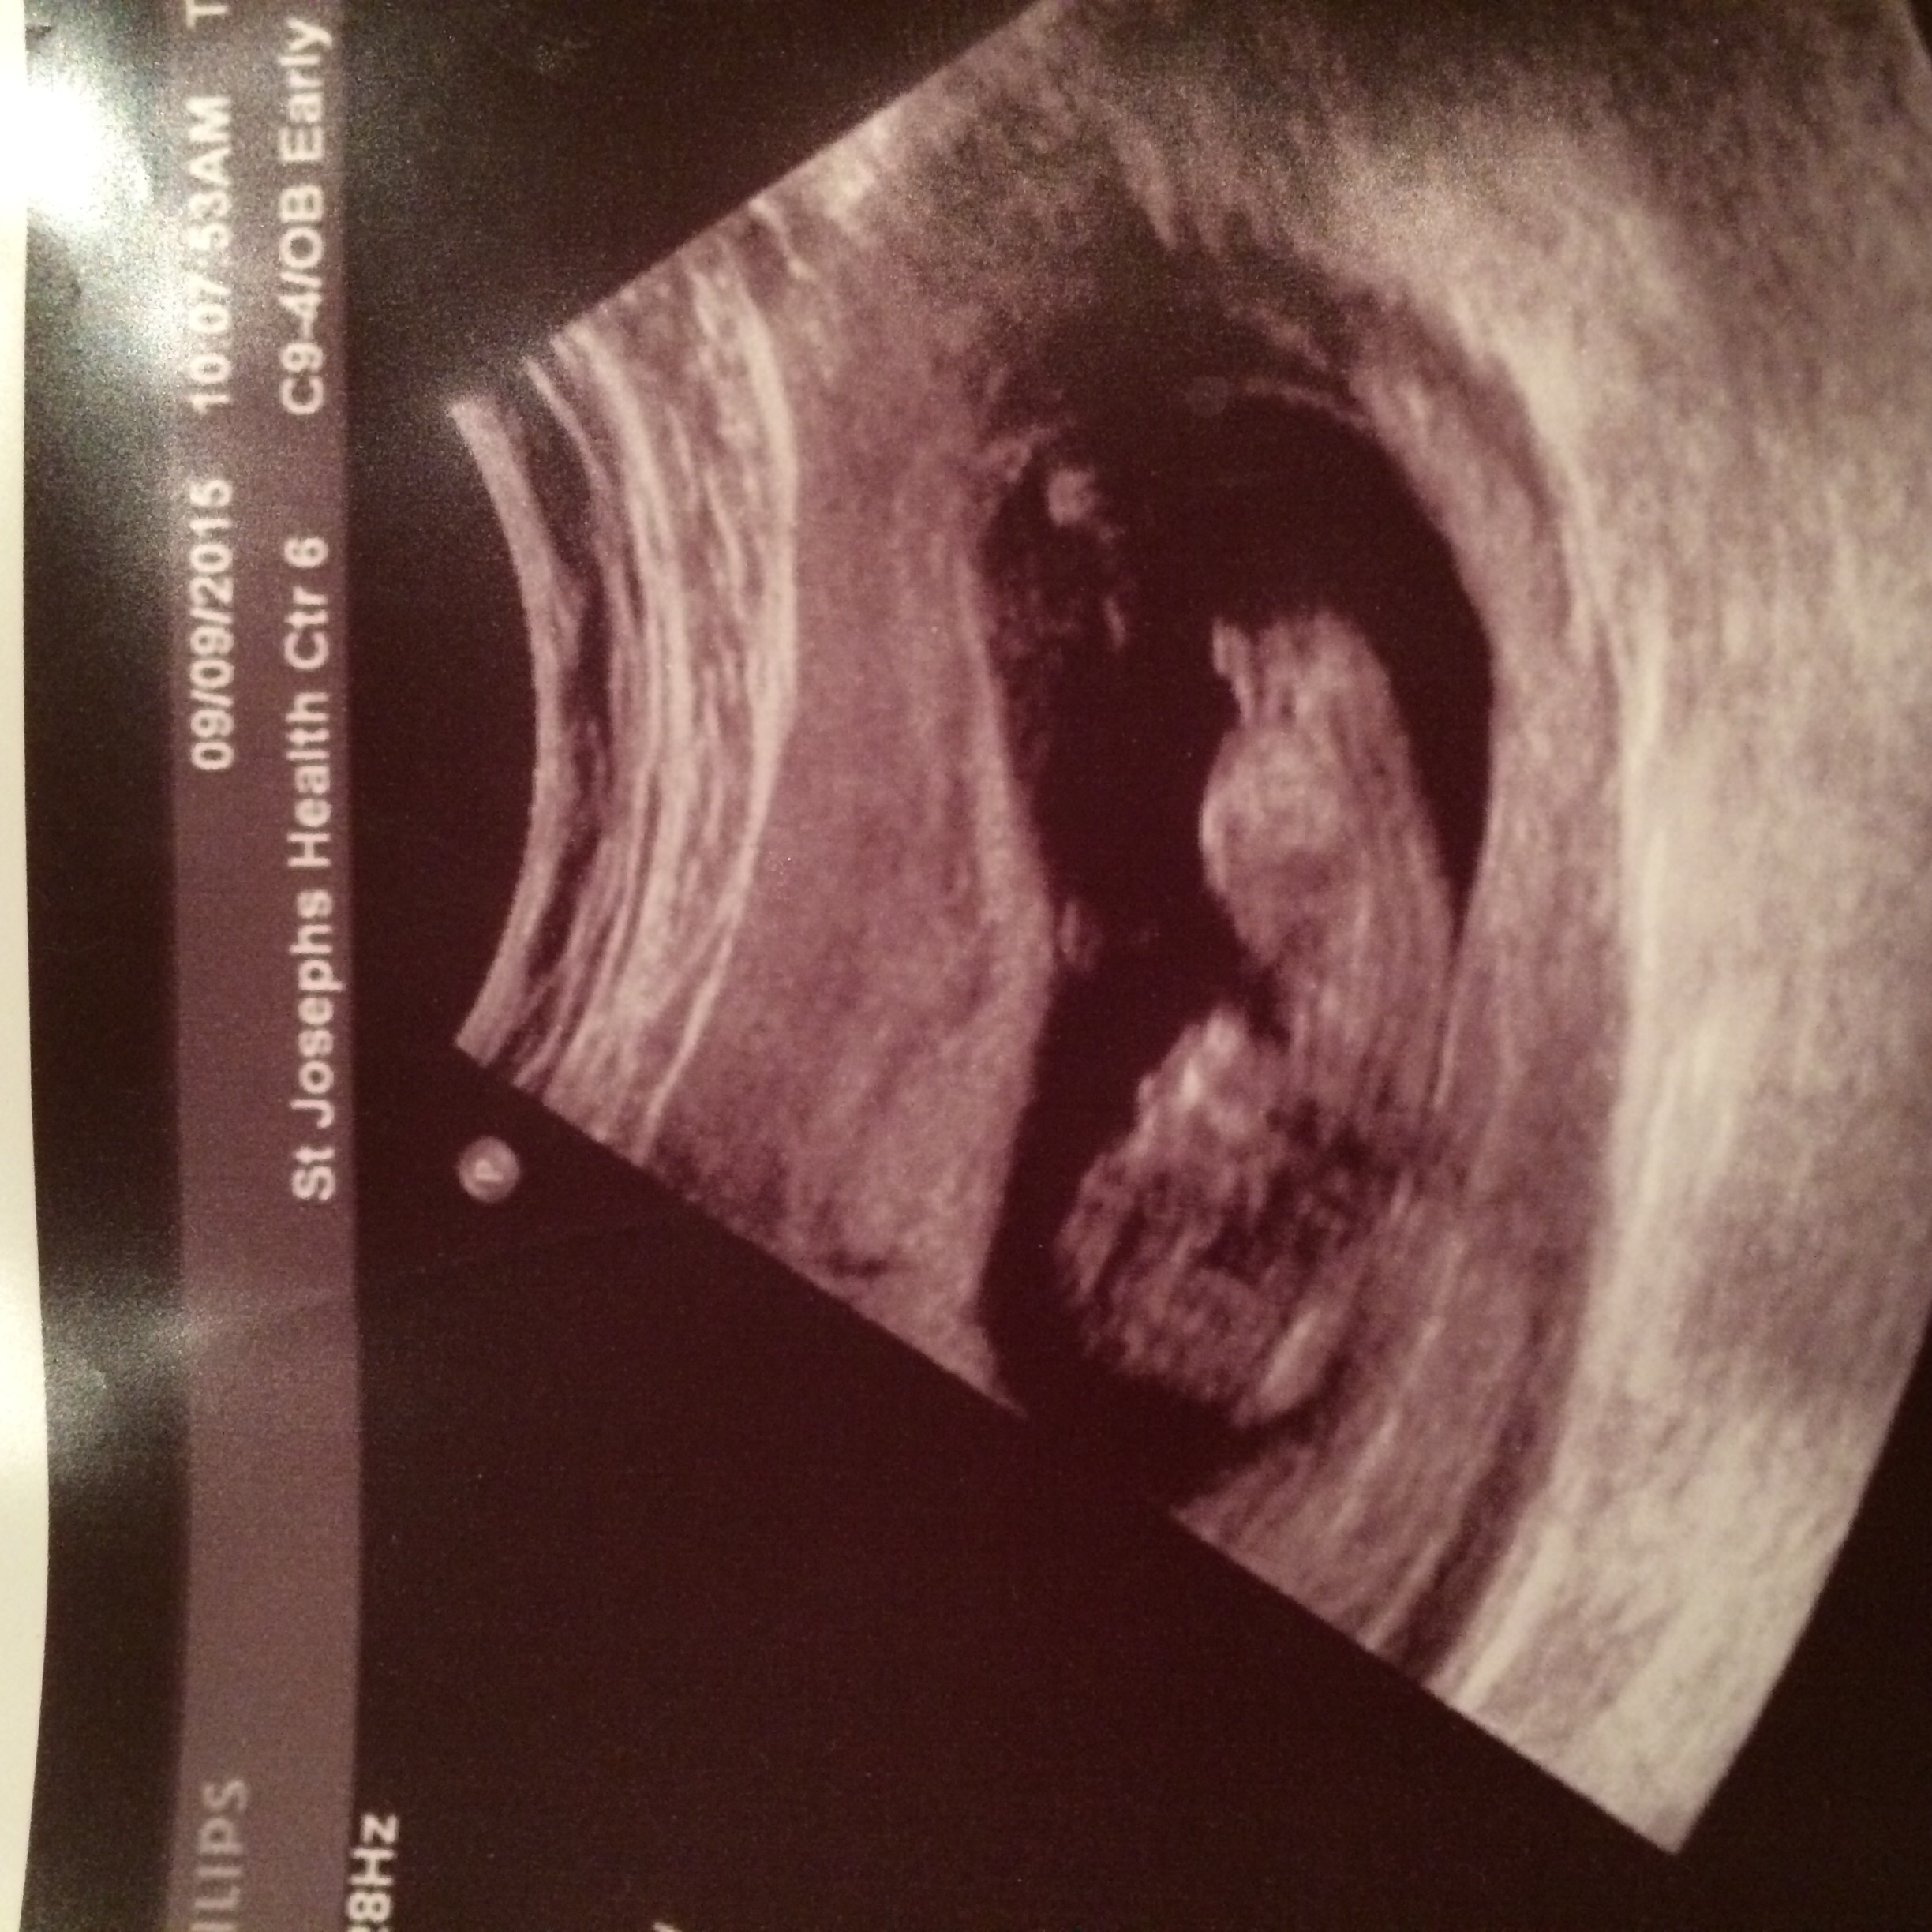

12w6dAttachment 27290:DS:Attachment 27291

These are all same baby lol between 12-12/6